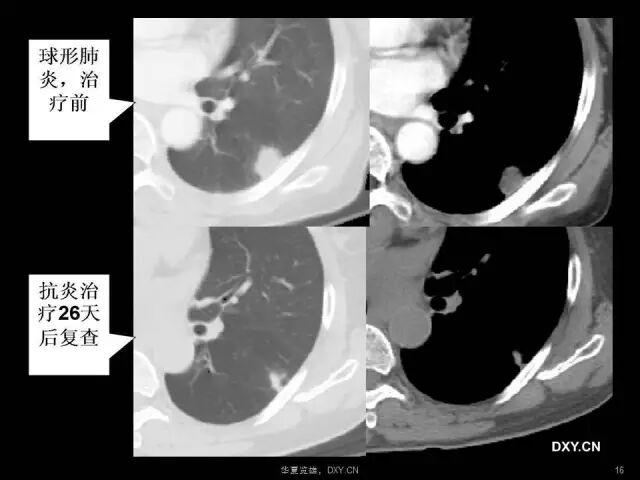

肺炎、肺癌、肺结核在影像学上的征象往往千变万化。